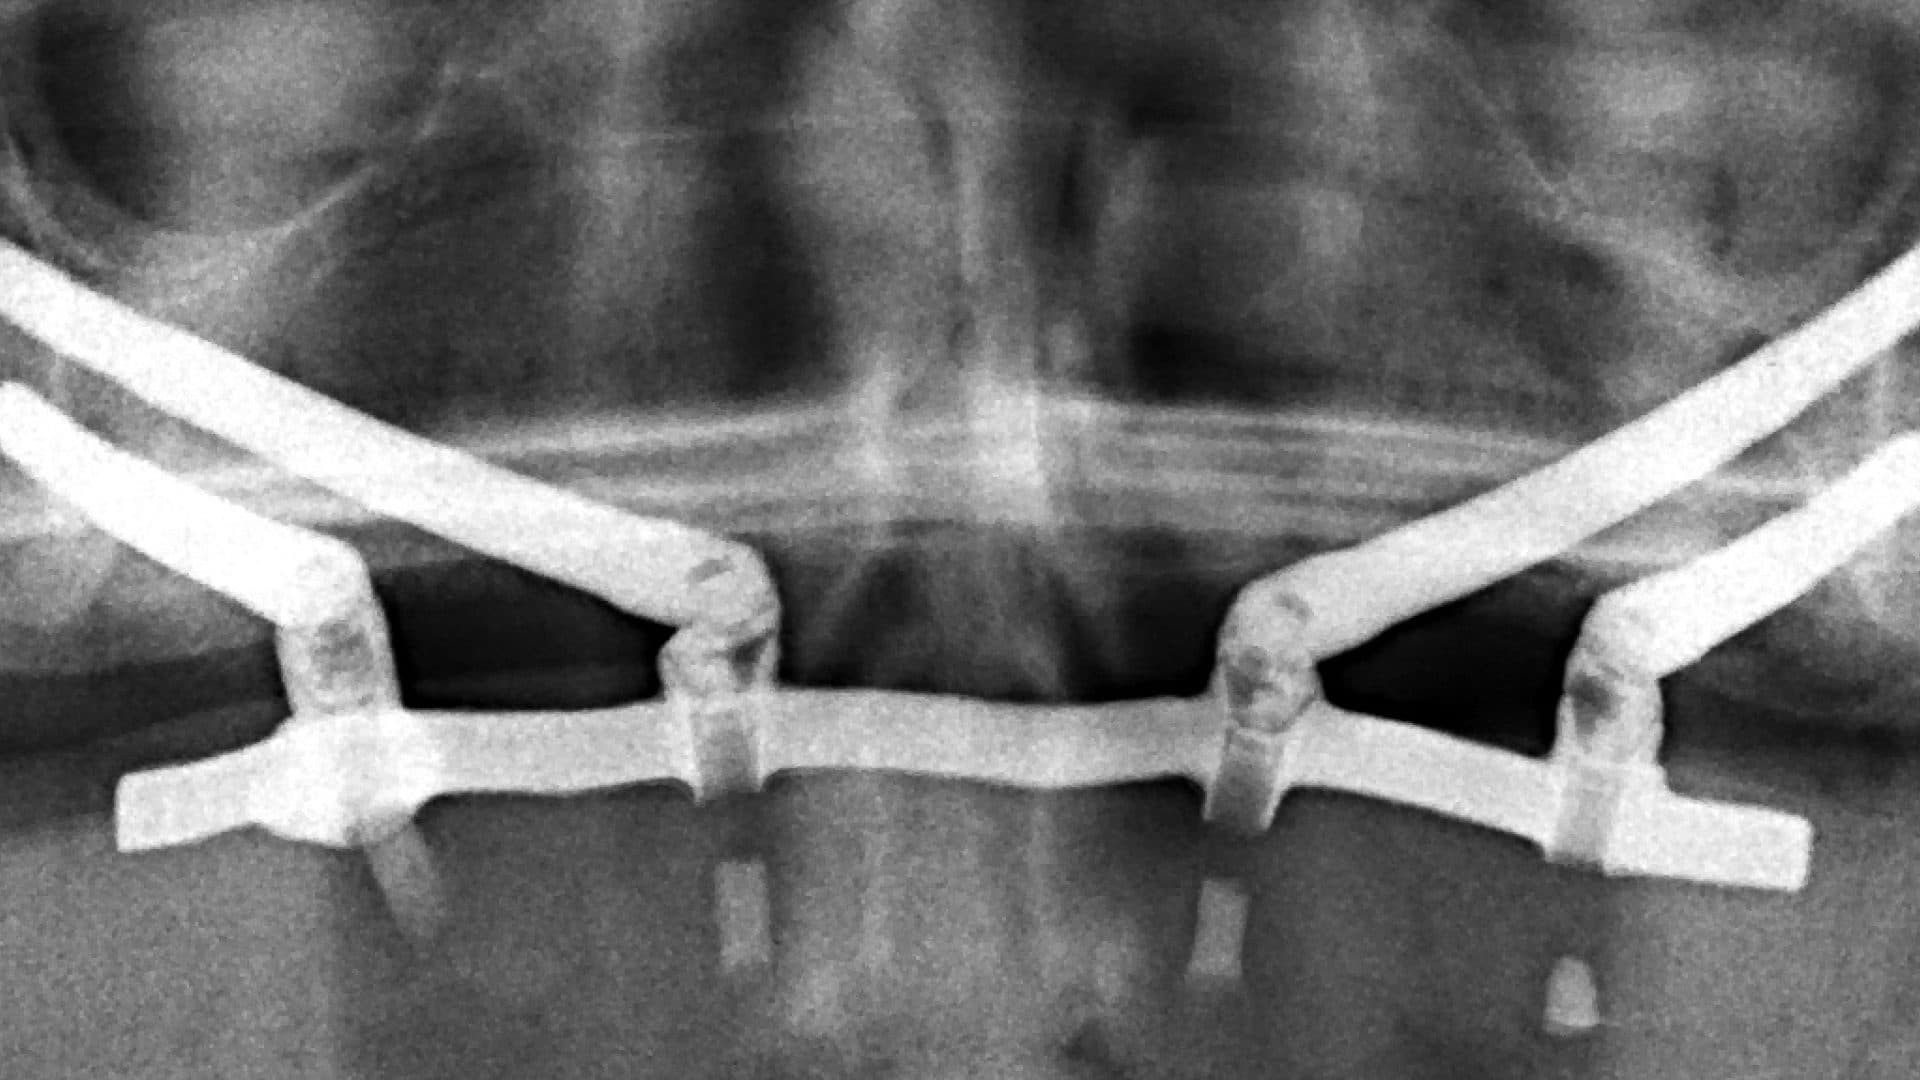

iii. Alignment on x-rays: there should be even spread, rigid connection between the implants, good bone levels, and the height of the prosthesis should be at least as tall as the shortest fixture (See pictures).

Examples Of Poor Standards